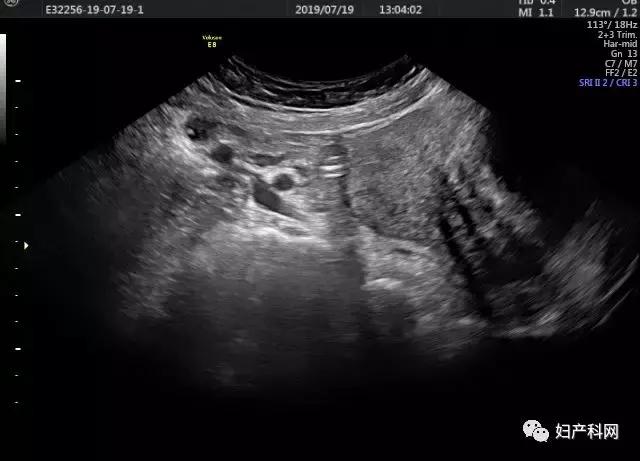

宫颈肌瘤术后超声造影

我们给这位客人选择的治疗方式为经皮卵巢囊肿穿刺+无水酒精固化+经皮子宫肌瘤微波消融术。术中从右侧卵巢囊肿内抽出褐色液体约70ml,使用无水酒精20ml固化15分钟后抽出。子宫肌瘤原本预计经阴道穿刺,但因为子宫肌瘤位置较偏,阴道穿刺后评估安全性存在问题,改为了经皮穿刺,60w功率下消融了18分30秒,子宫肌瘤基本达到完全消融。